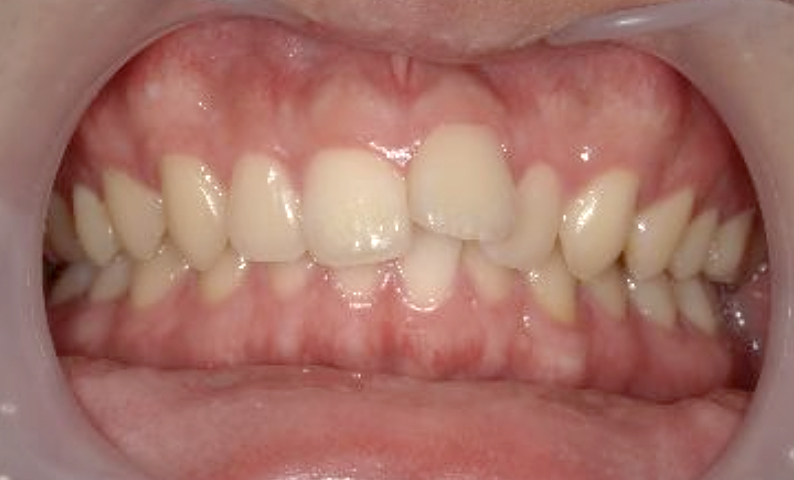

症例_002 上顎だけの部分矯正

治療期間:6ヶ月金額:24万円+税女性出っ歯上の前歯だけ

| Before | After |